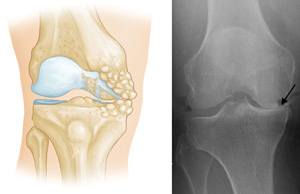

(Left) Osteoarthritis that is limited to the medial compartment. (Right) This x-ray shows severe osteoarthritis with "bone-on-bone" degeneration in the medial compartment (arrow).